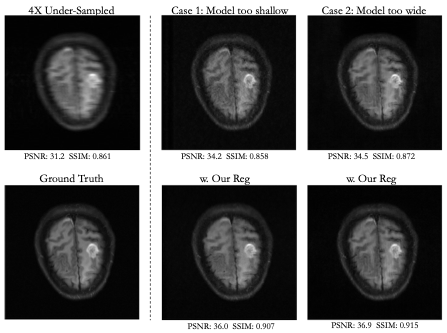

Visual and numerical results for the multi-coil knee and brain datasets under 4x and 6x acceleration are shown in Figs. 2-5 and Tab. 1. We tested U-Net architectures with typical widths (128 vs. 256 channels) and depths (3 levels vs. 5 levels). Additional results for total-variation (TV) regularized DIP [7] are shown in Tab 1. Figs. 2-5 indicate that suboptimal architectures lead to severe artifacts in the reconstructed images (top rows). Utilizing our regularization strategy, we observe appreciable improvements in image quality over the baselines, especially for 4x acceleration. Notably, the extent of improvement is similar regardless of the architecture. This suggests that controlling the frequency biases of the network architecture via proper regularization might be as effective as modifying the architecture in DIP based reconstruction. In contrast, TV regularization does not exhibit comparable performance. Our strategy works consistently on MR images acquired from different organs (i.e., knee and brain).

Fig 4. Results for a 4x under-sampled multi-coil brain scan. Our regularization strategy improves reconstruction over architectures that are too shallow (3-level UNet) or too wide (256 channels/layer).